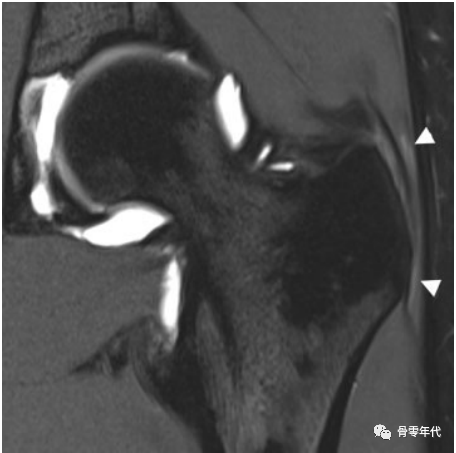

在这位27岁患有凸轮撞击的女性患者中,在脂肪饱和质子密度加权冠状关节造影术中,轻微的转子周围高信号(箭头)是一种常见的表现,没有大转子疼痛综合征。